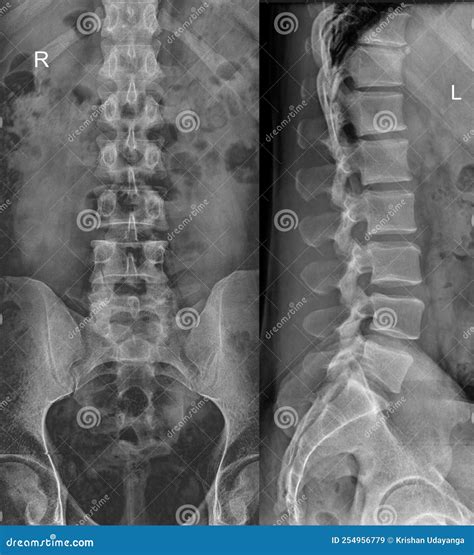

Dealing with persistent discomfort in your spine can be an overwhelming experience, leading many people to seek professional medical imaging. A back X-ray is often the first diagnostic step physicians recommend when assessing structural issues, injuries, or chronic pain in the vertebral column. By using a small dose of ionizing radiation, this imaging technique produces detailed pictures of the bones, allowing doctors to visualize the alignment, density, and integrity of your spine. Whether you are dealing with a sports injury, potential scoliosis, or long-term degenerative conditions, understanding what to expect during this procedure can significantly reduce anxiety and help you advocate for your own health.

When you arrive for your appointment, the process is generally straightforward and fast. A radiologic technologist will guide you through the necessary positions to ensure the best possible images are captured. Depending on the specific area of concern—cervical (neck), thoracic (upper back), or lumbar (lower back)—you may be asked to stand, sit, or lie down on a table.

To provide a clear picture, the technologist may ask you to hold your breath briefly or shift into different angles. This is crucial for capturing both the front-to-back (anteroposterior) and side (lateral) views of your spine. The entire process typically takes only a few minutes, making it a highly efficient diagnostic tool.

Thoracic Spine Rib attachment, upper back alignment.

Lumbar Spine Lower back pain, sciatica, disc height.

Interpreting Your Results

Once the images are taken, a radiologist reviews the back X-ray for any abnormalities. They look for evidence of bone spurs, narrowing of the disc spaces, compression fractures, or irregular spinal curves. These findings are then compiled into a formal report, which is sent back to your primary healthcare provider or the specialist who ordered the test.